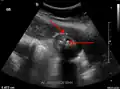

Right upper quadrant abdominal ultrasound is most commonly used to diagnose cholecystitis.[1][26][27] Ultrasound findings suggestive of acute cholecystitis include gallstones, pericholecystic fluid (fluid surrounding the gallbladder), gallbladder wall thickening (wall thickness over 3 mm),[28] dilation of the bile duct, and sonographic Murphy's sign.[13] Given its higher sensitivity, hepatic iminodiacetic acid (HIDA) scan can be used if ultrasound is not diagnostic.[13][14] CT scan may also be used if complications such as perforation or gangrene are suspected.[14]

Abdominal ultrasonography showing gallstones, wall thickening and fluid around the gall bladder -

Acute cholecystitis as seen on ultrasound. The closed arrow points to gallbladder wall thickening. Open arrow points to stones in the GB -